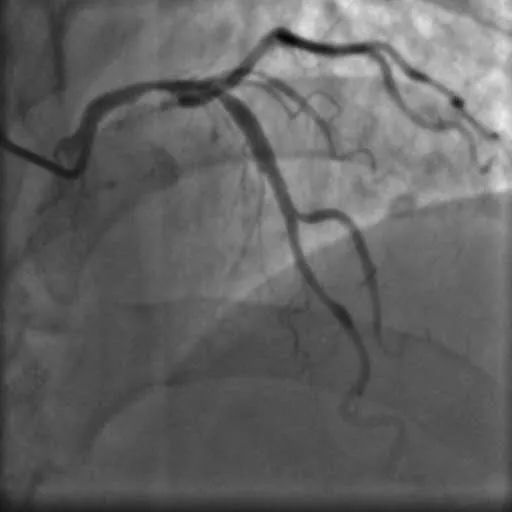

入院后,杨大爷很快在心血管介入中心进行了冠状动脉造影及血管内超声检查术,结果显示:左主干末端至前降支近段,回旋支开口都有严重狭窄且伴钙化。如果再推迟入院几天,很有可能发生猝死。

造影及血管内超声显示两枚支架均贴壁良好,前降支及回旋支开口管腔狭窄显著改善,前向血流良好。

造影图